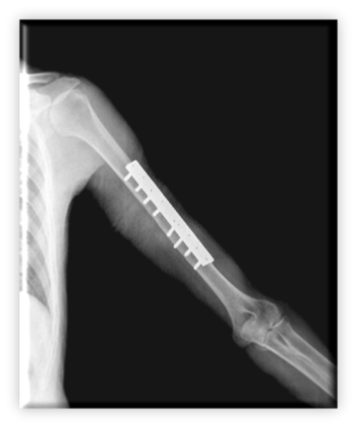

Αντίστοιχο κάταγμα διάφυσης αντιμετωπισθέν με πλάκα, βίδες και τελική πόρωση του κατάγματος